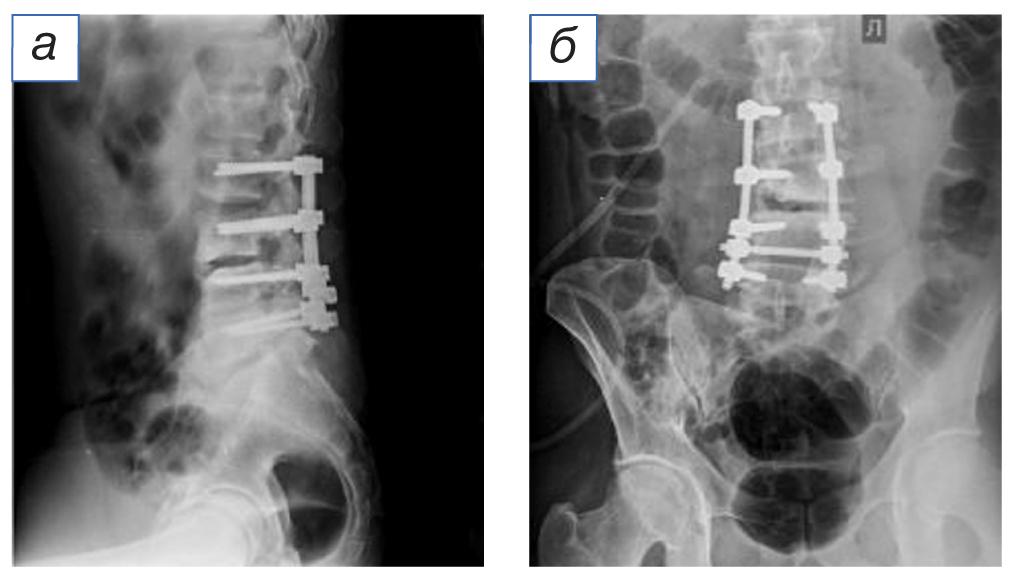

Оперативное вмешательство

Проведено плановое оперативное вмешательство для устранения стеноза позвоночного канала с микрохирургической декомпрессией корешков спинного мозга на уровне LIII–LIV, LIV–LV справа. Фораминотомия по ходу спинномозгового корешка L4 справа. Демонтаж нестабильной металлоконструкции. Задняя стабилизация LII–LIII–LIV–LV 8-винтовой транспедикулярной системой и двумя межтеловыми кейджами. После обработки операционного поля под эндотрахеальным наркозом в положении больного на животе по средней линии спины выполнен разрез кожи и подкожной клетчатки в проекции остистых отростков LII–LV (14 см). Иссечён старый послеоперационный рубец. Паравертебральные мышцы скелетированы до дужек и суставных отростков сегмента LII, LIII позвонков. Из рубцов выделена металлоконструкция на уровне LIV–LV. Произведён демонтаж фиксирующих гаек, удалены продольные стяжки. Правый верхний транспедикулярный винт нестабильный (определяется перелом винта на границе резьбы и тюльпана). Винт удален. Рана повторно санирована растворами антисептиков. Произведена гемиламинэктомия LIII справа. Осуществлен доступ в позвоночный канал. С применением микрохирургической техники произведена декомпрессия дурального мешка и корешковых нервов на уровне стеноза. Медиальная фасетэктомия LIII справа с последующей фораминотомией по ходу L4 корешка. Радикулолиз, корешок отведен медиально, обнажена задняя продольная связка на уровне LIII–LIV. Определяется костно-хрящевой узел, компримирующий латеральные отделы позвоночного канала и обусловливающий фораминальный стеноз с компрессией корешкового нерва. Выполнена резекция костно-хрящевого узла. Паравертебральные мышцы справа скелетированы до основания поперечных отростков LII, LIII позвонков. В стандартных точках произведена подготовка каналов для введения транспедикулярных винтов в тела LII, LIII позвонков. Под рентгеноконтролем установлены полиаксиальные транспедикулярные винты (6,5×50, 4 штуки). Головки транспедикулярных винтов отрегулированы в положение, соответствующее изгибу позвоночника. Продольные тяги смоделированы в соответствии с лордозом позвоночно-двигательного сегмента, и осуществлена стабилизация поясничного отдела позвоночника с уровня LII до LV. Редукционным инструментом латеральное смещение LIII позвонка устранено. Произведена фиксация продольных стяжек к винтам заглушками-фиксаторами. Дополнительно стяжки скреплены между собой поперечным фиксатором. На контрольных рентгенограммах состояние имплантируемой металлоконструкции удовлетворительное (рис. 4). Рана послойно ушита наглухо.

Рис. 4. Послеоперационная рентгенография в боковой (а) и прямой (б) проекциях: 8-винтовая система транспедикулярной фиксации LII–LIII–LIV–LV.

Fig. 4. Postoperative radiography in lateral (а) and direct (б) projections: 8 screw transpedicular fixation system LII–LIII–LIV–LV.